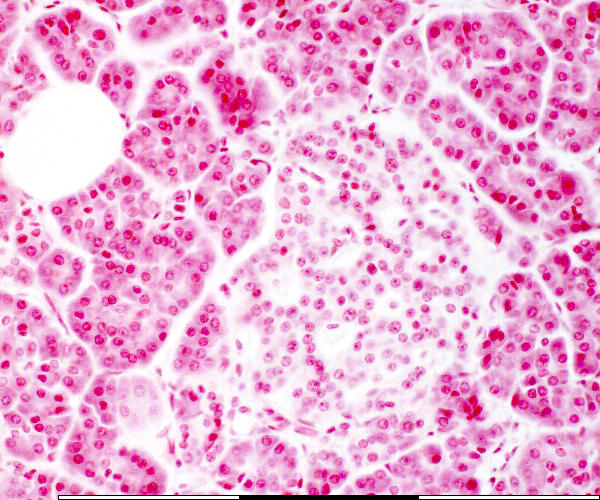

High magnification of the pancreas

© mei 2007 marius loots